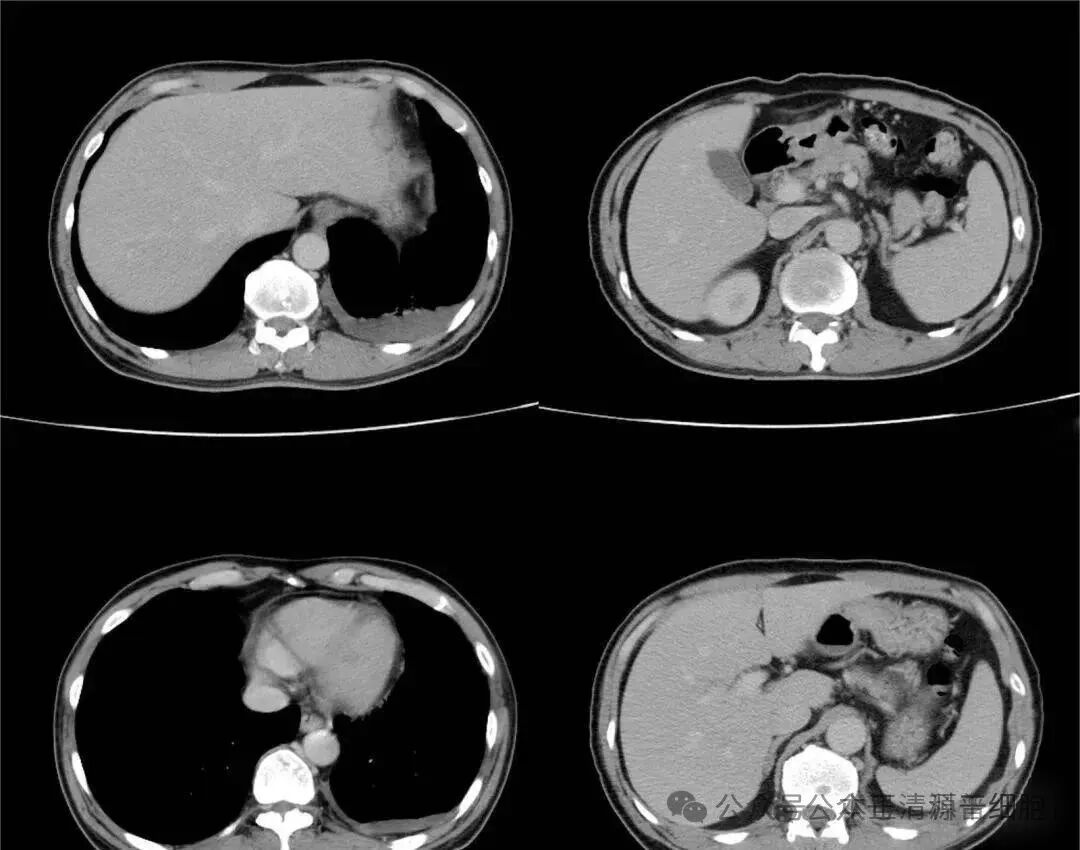

“医生,我的体检报告上显示我是肺部结节,需要做手术吗?是良性还是恶性的呀?”对于体检中发现的肺部结节,许多人都会惊慌失措,担心自己是得了肺癌。经过多家医院检查,得知自身结节不具备肿瘤的典型特征,才稍感安慰。但是也产生了新的难题,因为每家医院给的诊疗方案各不相同,有的说要随访观察,保守治疗,有的却主张进行手术,以绝后患,这到底该听谁的呢?正常情况下,医生会根据结节的大小、形态来判断结节的性质,从而给出治疗方案。目前认为,直径小于8毫米的结节在短时间内发展成为肺癌的可能相对较小。所以一般情况下,小于8毫米的肺部结节会以随访观察为主,根据动态变化随时斟酌对策。如果不知结节是否病变之前,贸然手术,等到最后发现结节可能一直会是良性时,这刀就白挨了。且手术还需承担各种风险,如切除的肺组织不可再生,手术后的肺部功能会降低……权衡利弊之下,接受医院观察随访,在结节病变之前及时手术切除,或许才是上上之策。对体积大于10毫米的肺部结节,医生一般会增强CT、PET-CT等功能显像的检查,来区分结节的良恶。若结节不规则,边缘粗糙,有毛刺,且在随访观察中,直径不断增大,就要警惕可能是恶性结节,需尽早手术治疗。当然,万事无绝对!对于小于8毫米且高度怀疑肿瘤性病变的的肺部小结节,尽管它生物学行为弱,发展较慢,有时几年都无变化或轻微增大,但也不能对它掉以轻心,因为它有转移播撒的可能,如果任其变大或者密度变高,再去斟酌处理,可能为时晚矣!如果一个小手术,就能解决肿瘤性肺部小结节浸润、转移、气道内播撒的风险,何乐而不为呢! 面对结节,想要切除,但是又怕是良性不会变坏,白挨一刀,但是揣着个随身“炸弹”整日又提心吊胆,那有什么办法既不用手术,又能解决结节的吗?结节有良恶之分,其中良性结节常见的有炎症、结核、真菌感染等。而免疫细胞正是人体清除病毒、细菌以及突变细胞、癌细胞的主力军,消灭结节中的肿瘤细胞,以及各种细菌,正是免疫细胞的职责。(注意!如果是炎性结节,不建议使用免疫细胞疗法,可用干细胞。)免疫细胞疗法,是将健康优质的免疫细胞回输到患者体内,增强其免疫功能,杀灭结节中的病原体和突变细胞,缩小甚至消除结节。44岁的王先生经过体检,发现右肺脏层胸膜表面之下(肺的内部),存在两枚磨玻璃结节,其中较大者直径有7.6mm,医生建议随访。王先生为此走访了很多专家医生,医生建议除了定期复查外,需提高自身免疫力。王先生通过朋友推荐使用了一个疗程的免疫细胞应用。治疗几个月后,王先生再次复查,很神奇,肺结节不见了。免疫细胞疗法,只需采取脐带或自身外周血,进行提取、培养、扩增免疫细胞,再回输体内,这种生物医学疗法既不伤害身体,又能解决结节。相信随着技术的发展,免疫细胞疗法将能够造福更多的患者。在生命面前人人平等。短短几十年,我们也许顺其自然的享受着生命的每一天,我们身边时常会听到某某某富翁突然离世或身患重病难以医治的例子,可是有些事情不能等,一定要趁早,健康是1,是人生的开始,0是成就,没有1,再多的0也都无的放矢。